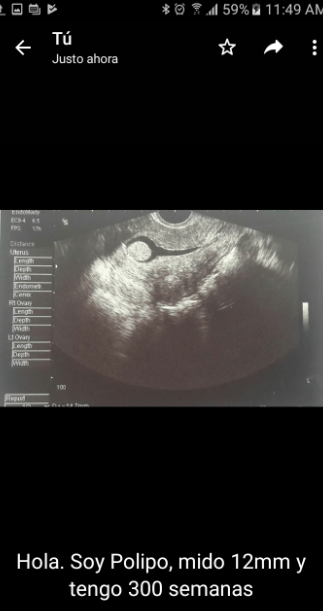

El preoperatorio se tarda una hora más; la sala en la que me van a operar está ocupada, imagino que es debido a alguna complicación. No tengo nada para leer, solo unos exámenes de sangre y orina que me sé de memoria y la ecografía de mi pólipo para que el doctor sepa dónde está y no me retire nada más.

El chat de mis amigas del colegio está lleno de imágenes como ésta acompañadas de un: «Hola les presento a Jacobo, tiene doce semanas y estamos muy felices».

Si aguzo la vista hasta puedo verle los ojos y el corazón, quisiera enviarles la foto que sostengo en mis manos: “Hola, soy pólipo, mido 12 mm y tengo 300 semanas, el sistema reproductivo de mi mamá está bastante comprometido, pero felicitaciones por Jacobo”.